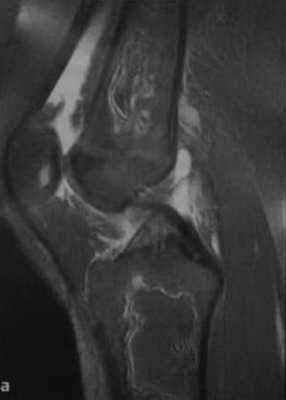

МРТ картина инфаркта костного мозга

- МРТ картина гонартроза 1 степени, синовита левого коленного сустава, признаки дегенеративных изменений передней связи, инфаркта костного мозга на границе н/3, с/3 диафиза бедренной кости.

Что покажут снимки МРТ кости при инфаркте

- В ранней стадии заболевания - отек (гипоинтенсивный на Т1-взвешенном изображении и гиперинтенсивный на Т2-взвешенном изображении)

- Позднее отграничение вдоль периферии пораженной кости (гипоинтенсивное на Т1 - взвешенном изображении; на Т2-взвешенном изображении - гиперинтенсивная линия по направлению к зоне некроза, соответствует грануляционной ткани)

- Гипоинтенсивная линия по направлению к здоровой кости (склероз, фиброз): признак двойной линии

- Накопление контрастного вещества периферической зоной

- При застарелых инфарктах кости интенсивность сигнала зоны некроза эквивалентна жировой ткани

- Периферическая зона типично извилистая, напоминает гирлянду.

а, b Инфаркт зрелого костного мозга. (а) Сагиттальная протонная плотно-взвешенная МРТ с подавлением МР-сигнала от жировой ткани. Изображение демонстрирует гирляндовидный склеротический край и центральный участок с сигналом жирового костного мозга. Множественные некротические зоны расположены преимущественно в метадиафизальной области, однако несколько находятся непосредственно рядом с суставом, в связи с чем имеется риск уплощения суставных поверхностей;